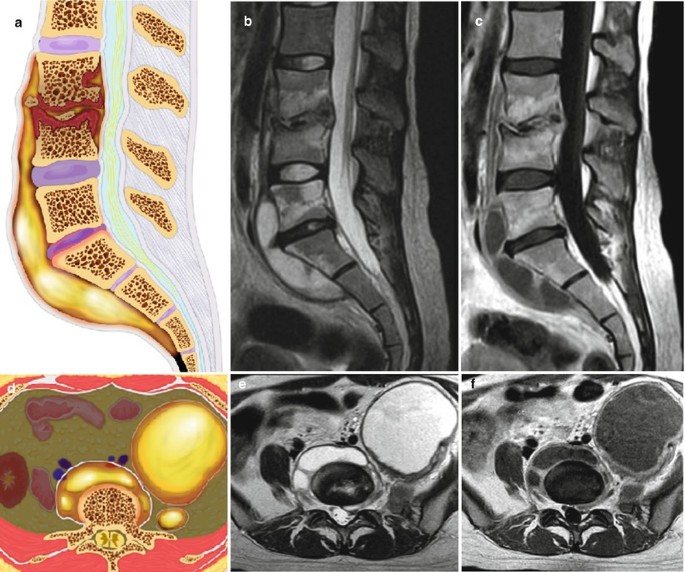

- A thorough diagnosis consists of imaging tests such as MRI or CT scans, blood tests to identify infection markers (elevated ESR, CRP), and a physical examination to evaluate pain and neurological function.